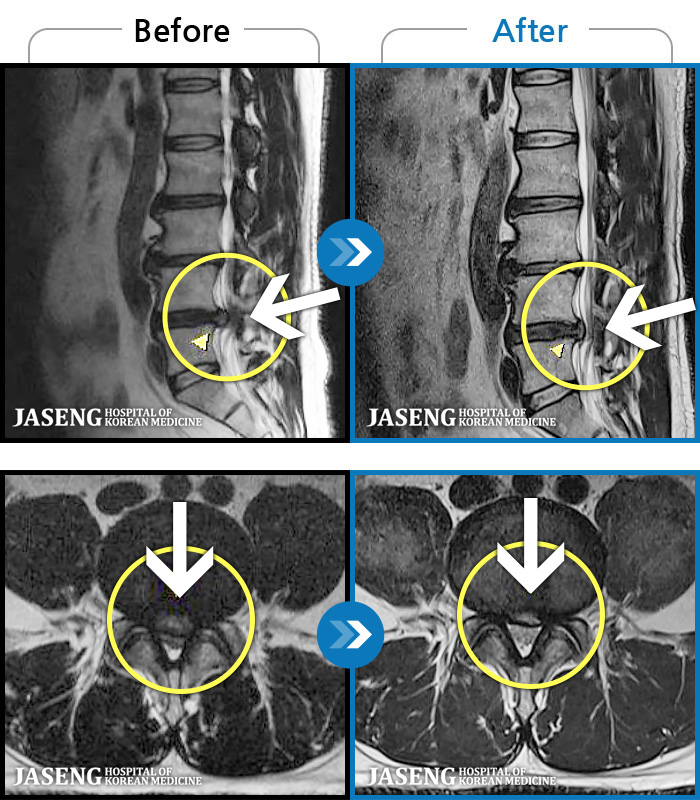

1,257 MRI ũ ʸ Ȯϼ.